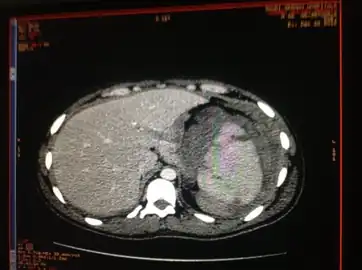

Traumatic rupture of the spleen on contrast enhanced axial CT (portal venous phase) -